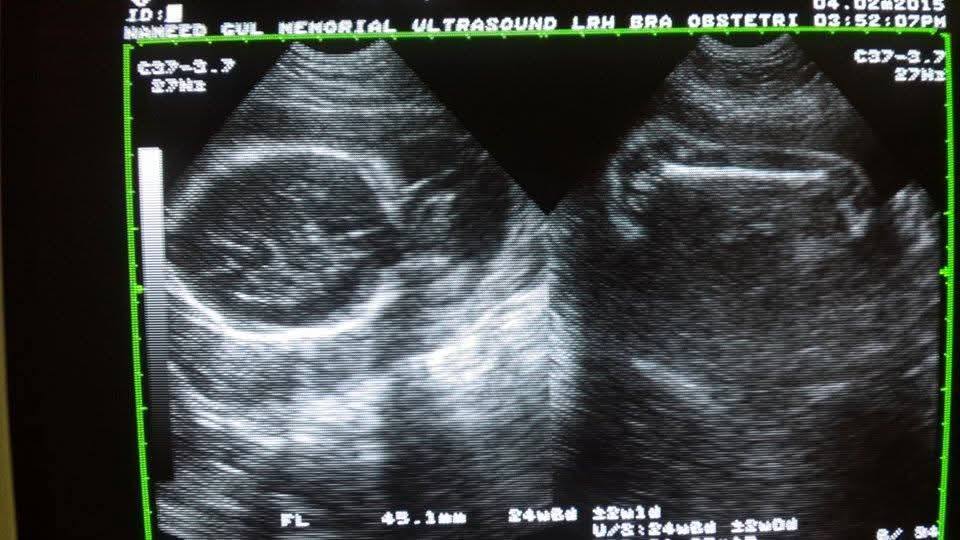

Our institutue provides high-quality ultrasound imagies for various diagnostic applications. these images serve as essential tools for accurate diagnostic and treatment planning.